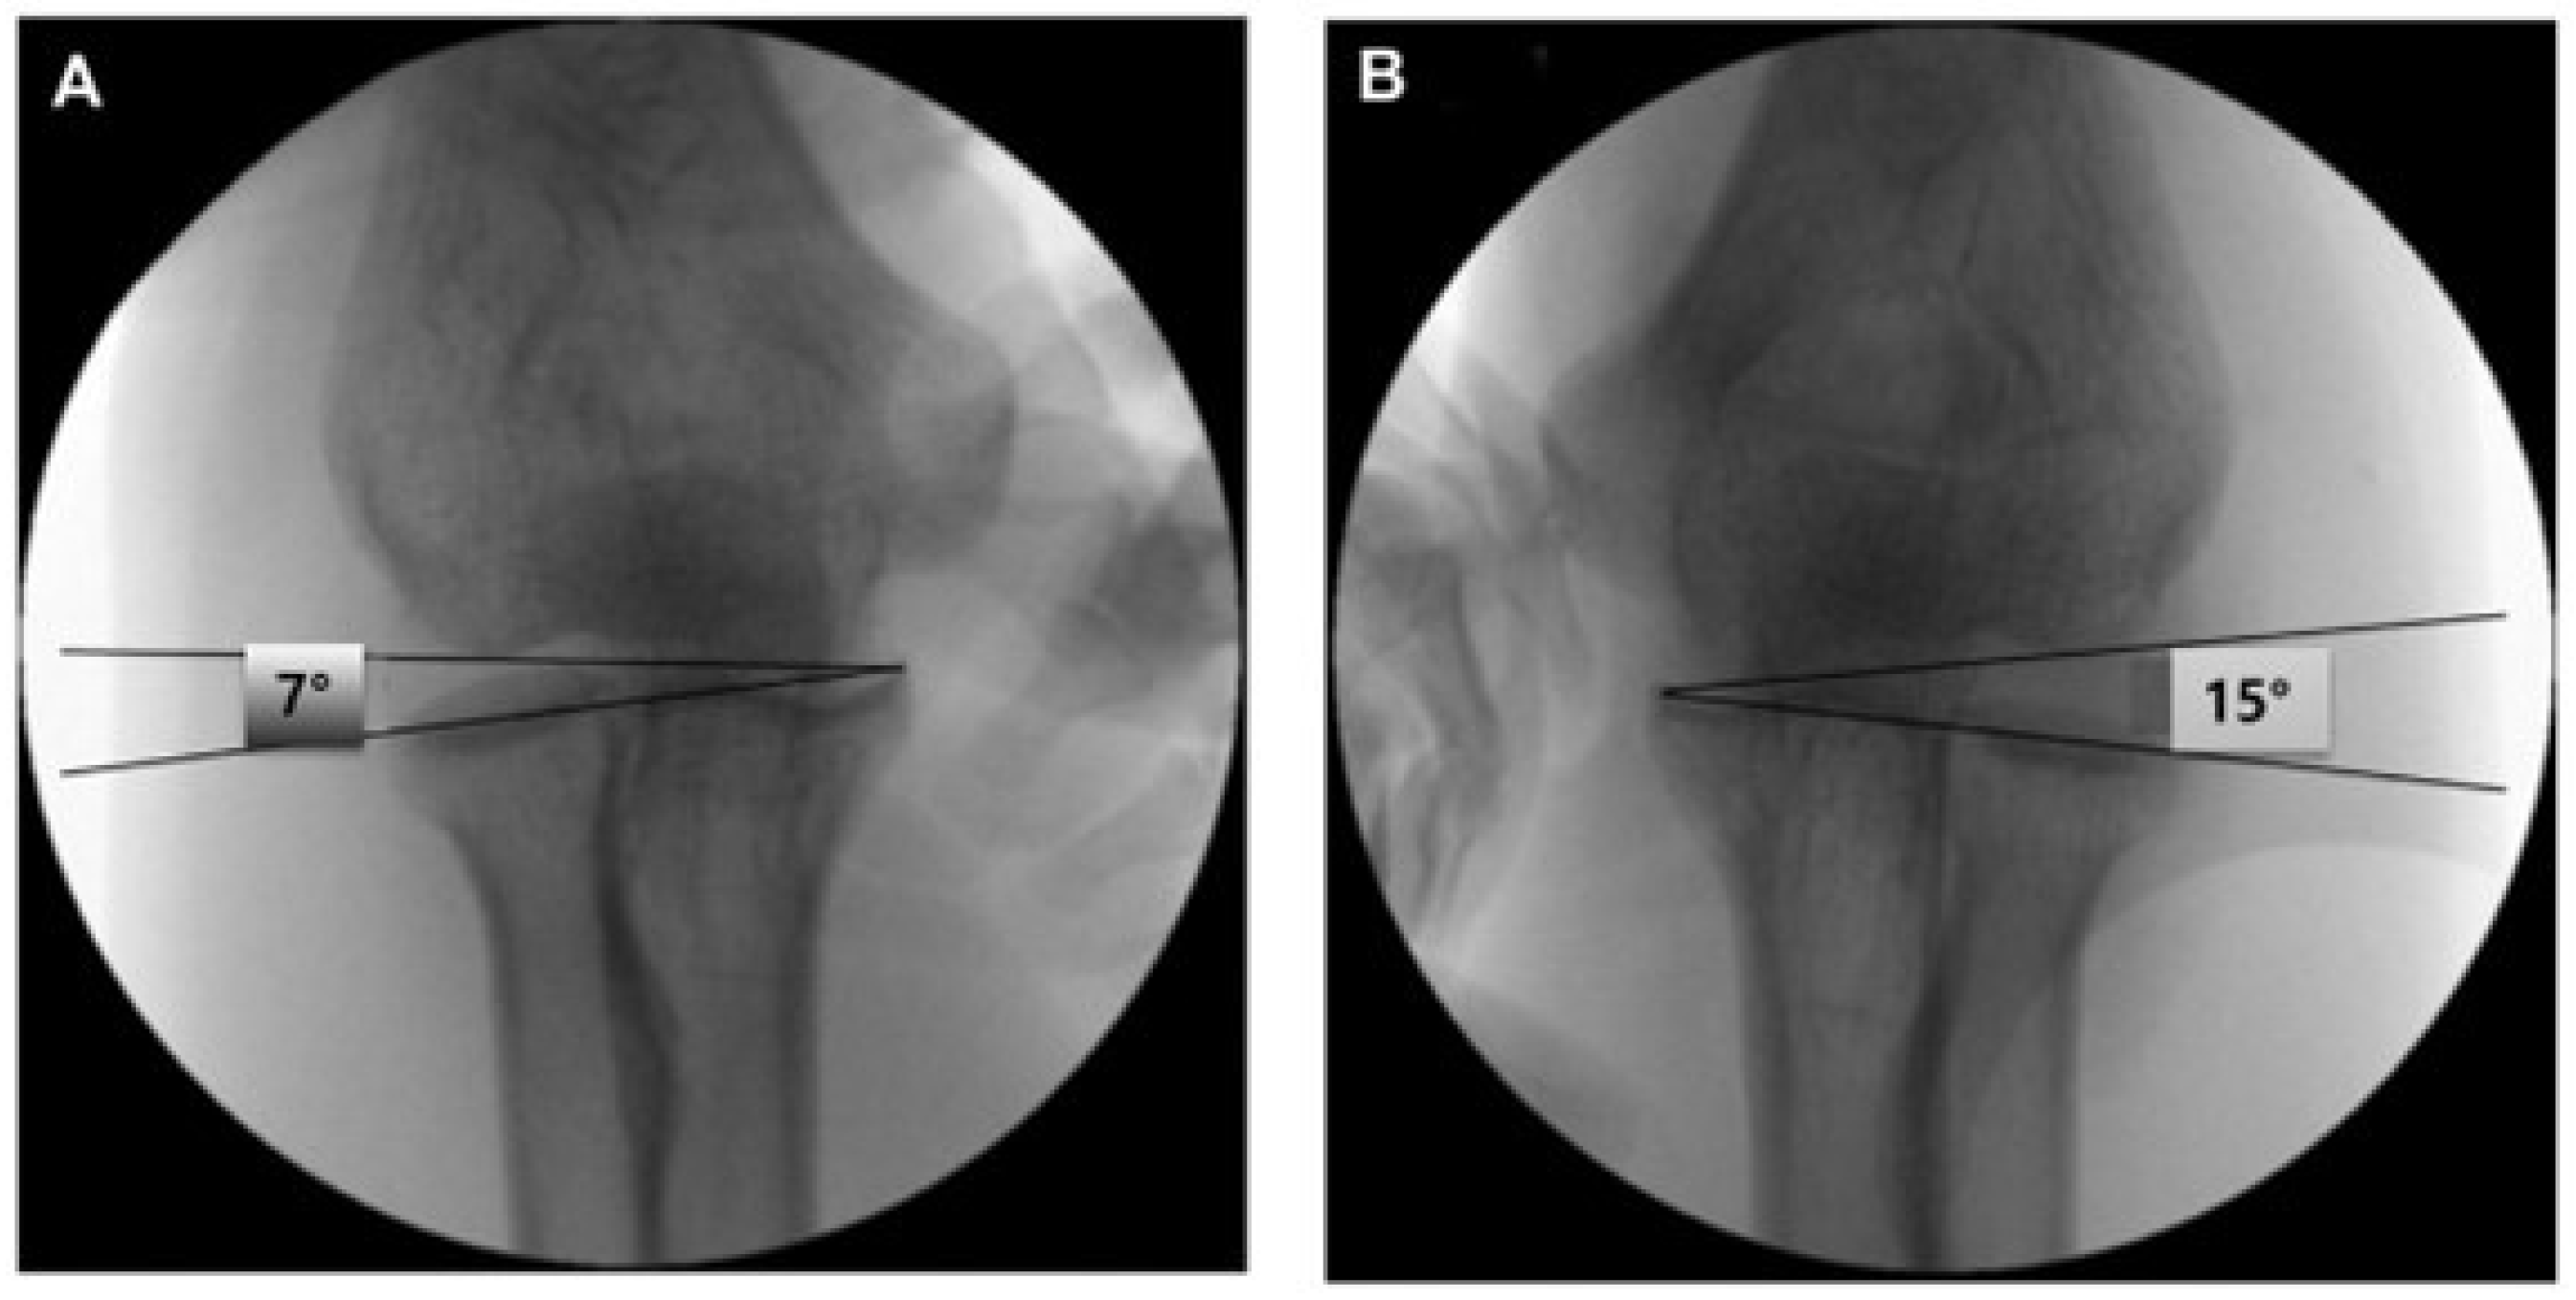

- A capitellum–sublime tubercle–radial head angle (CSRA) greater than 5° compared with the contralateral side. (Figure 2) This threshold was adopted based on previous studies that demonstrated its diagnostic utility in detecting subtle lateral elbow instability [13]. The CSRA measurement reflects subtle changes in joint alignment, aiding diagnosis of minor instability in this population.